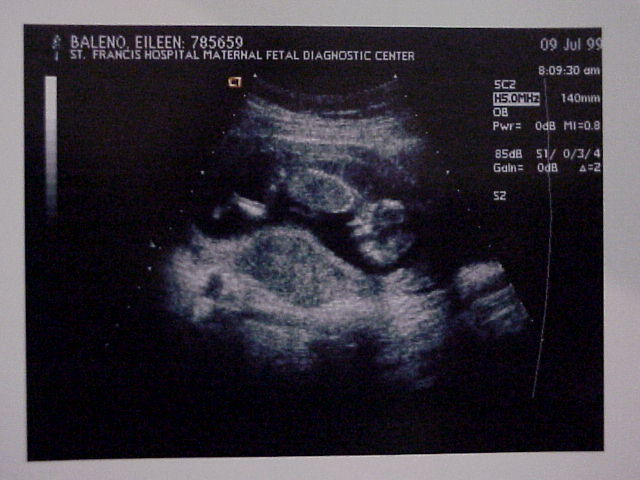

The first picture of the baby.